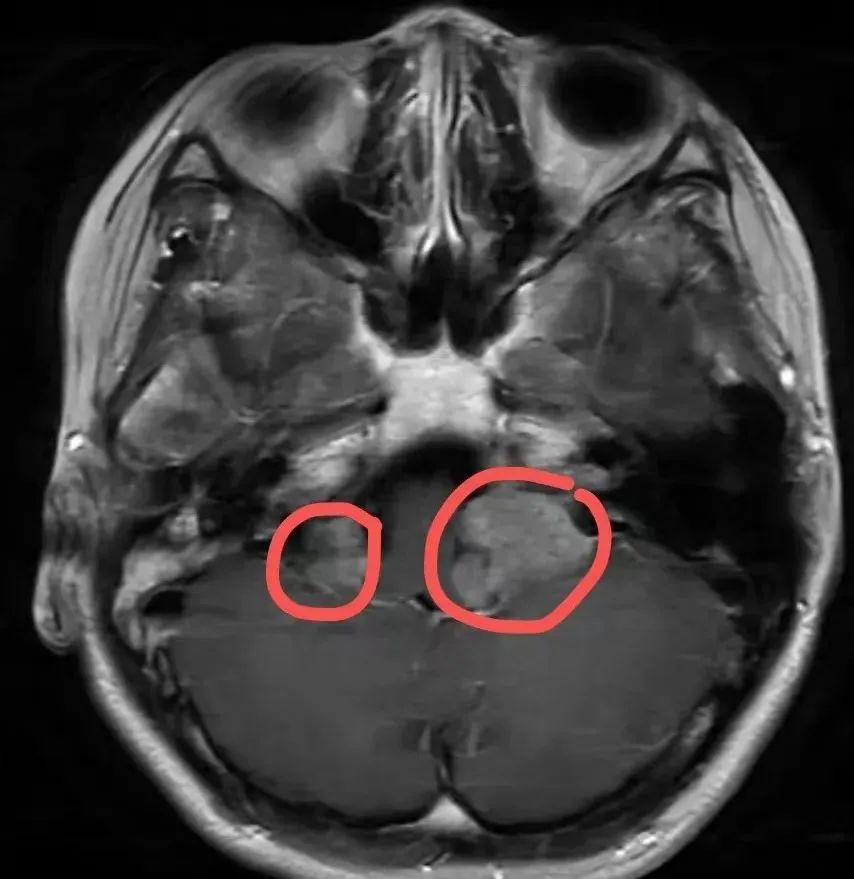

当时小叶即将报名参加高考,听力损伤让她特别焦虑。经过检查,发现这不是一个简单的耳朵问题。小叶两侧颅内的前庭神经正在被肿瘤“侵袭”,这是她听力损伤的罪魁祸首。小叶患有一种罕见的遗传病——神经纤维瘤病。

综合评价后,医生认为小叶右侧的听神经瘤目前比较稳定,可以选择定期随访观察。但左侧听神经瘤体积较大,对周围组织造成明显压迫,可引起颅内高压等症状,严重影响生活质量。

最终,医生对小叶进行了微创左侧听神经瘤切除术,成功切除肿瘤。手术后恢复顺利,小叶顺利完成高考。